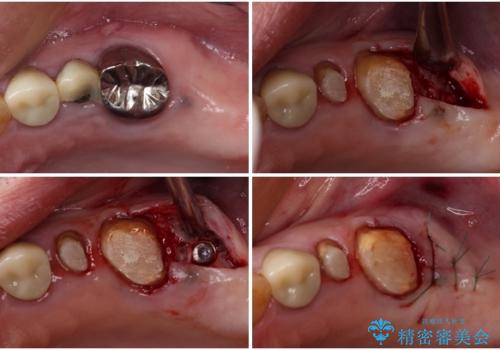

改めて診療を行ったところ、歯根破折が認められ、抜歯後にインプラント治療を行うこととしました。

下顎大臼歯の抜歯決断までに時間がかかったため、治療期間はやや長くなりましたが、安定した咬み合わせとなり、痛みもなく安心して噛めるようになりました。